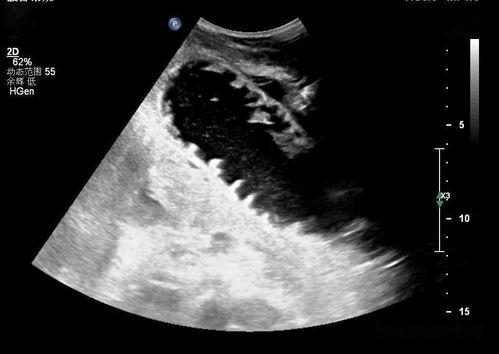

当肠梗阻发生时,首先会出现肠管扩张的情况。在超声检查中,你可以看到肠管壁增厚,肠腔内出现液性暗区,就像一条条小溪在肠道里流淌。

肠梗阻还会导致肠腔内气体增多。在超声检查中,你可以看到肠腔内出现多个液气平面,就像肠道里装满了气泡。

在这段视频中,你可以看到:

- 肠管扩张的情况,就像一条条小溪在肠道里流淌;

- 肠腔内气体增多,出现多个液气平面;